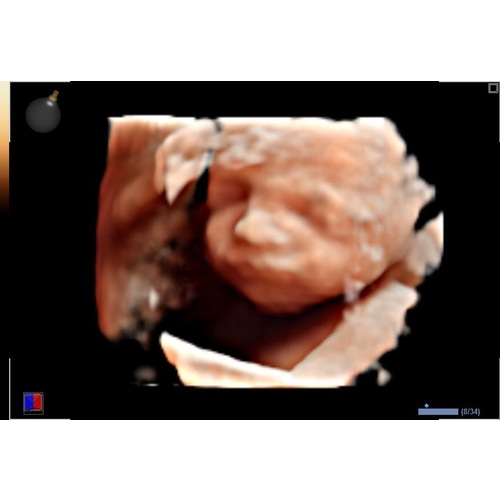

Ze staan er volgens mij elke dag! Kost 50 euro krijg je twee foto's geprint en een USB stick met alle foto's. ( Het is trouwens ook allemaal voor je goede doel ) Ik vond het echt leuk en de moeite waard ook al zie je nog niet hoe de baby er verder precies uitziet. Juist een toffe ervaring en doe het met 28 weken gewoon weer